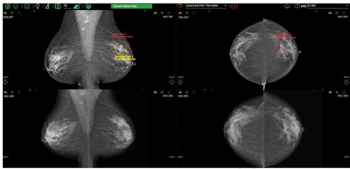

While researchers noted no significant impact on sensitivity rates, they found that access to a patient’s prior mammograms resulted in a nearly 15 percent increase in sensitivity for current mammography interpretation.